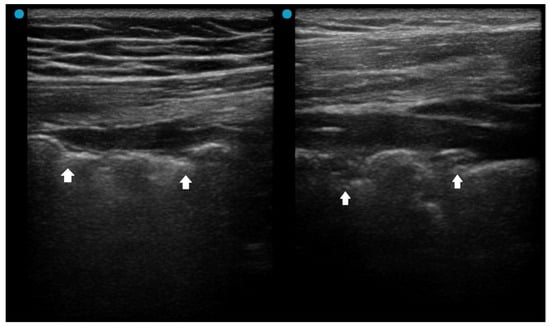

In addition to standardized lateral cephalometric radiographs, comprehensive assessment using dental cone-beam computed tomography (CBCT) and CT has become commonplace in the diagnosis and treatment of jaw deformities. Simulation based on cephalometr...